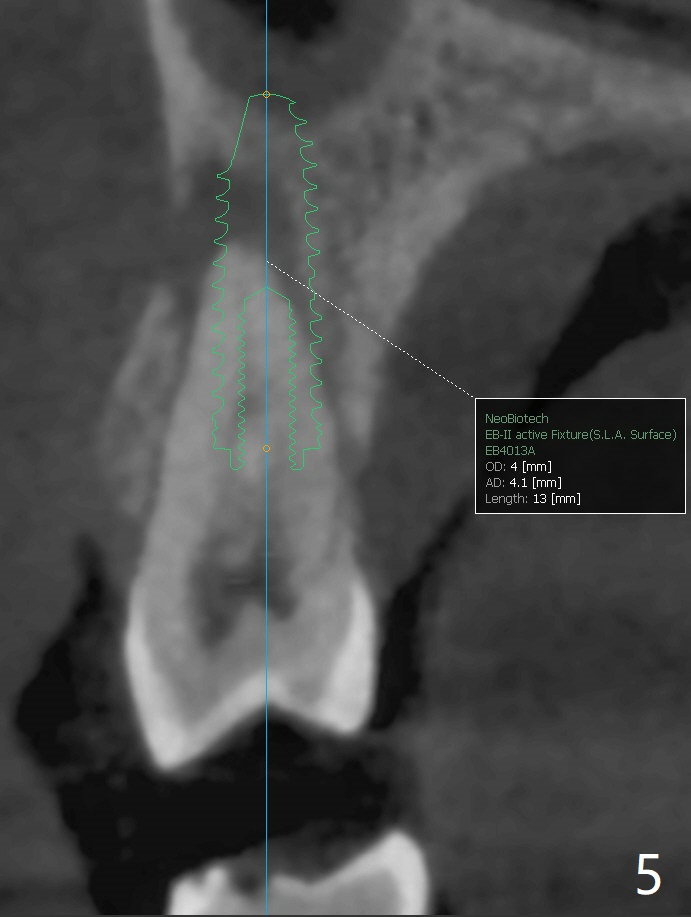

A 52-year-old woman had palatal periodontal infection at #2 a half month earlier (Fig.1,2), which was treated with Arestin. When she returns, the tooth #4 has palatal subgingival oblique fracture (Fig.3 <), interfering with mastication. Due to emergency, free hand immediate implant is planned. The buccal apical defect (Fig.3 *) will be repaired with PRF membrane (x1) and allograft after osteotomy (with gauze in place). A 4.5x20 mm tissue-level implant will be placed (Fig.4) instead of a bone-level one (Fig.5).